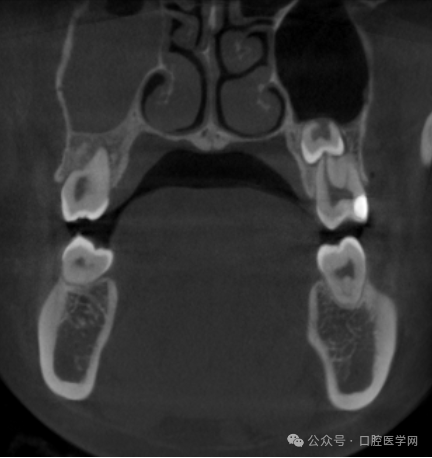

张领辉医生:内镜下经上颌窦入路拔除上颌阻生牙